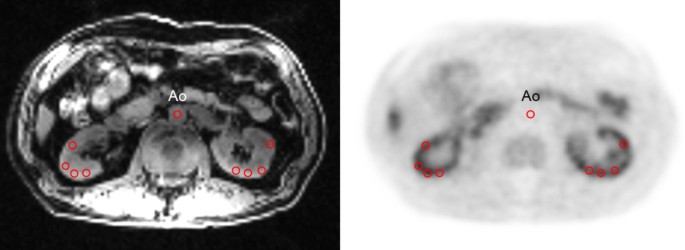

Ten circular ROIs, 10 mm in diameter, were placed on each kidney using 3–6 slices (three slices were used for most subjects, and four to six slices were used in cases with severe renal atrophy) on LAVA-FLEX MRI images acquired during dynamic PET to obtain the cortical RBF and SUV (Fig. 1). To evaluate the renal tissue OS quantitatively, the RBF-adjusted SUV was calculated from the SUV with a correction for RBF. In this new parameter, SUV is corrected to avoid the influence of RBF on tracer accumulation, which would delineate the relative OS level in the tissue14,17,19, and we define it as adjusted OS index (aOSi), i.e., aOSi = [SUV/ RBF (mL/min/100 g)] x 100 (g), where the regional RBF was corrected into the unit of (mL/min/g). aOSi images were also calculated using the same equation.

Example of ROIs set at the same slice level on LAVA-FLEX MRI (left) and PET (right) images. The locations of ROIs are exactly the same because the two images were acquired simultaneously. Ao indicates abdominal aorta.